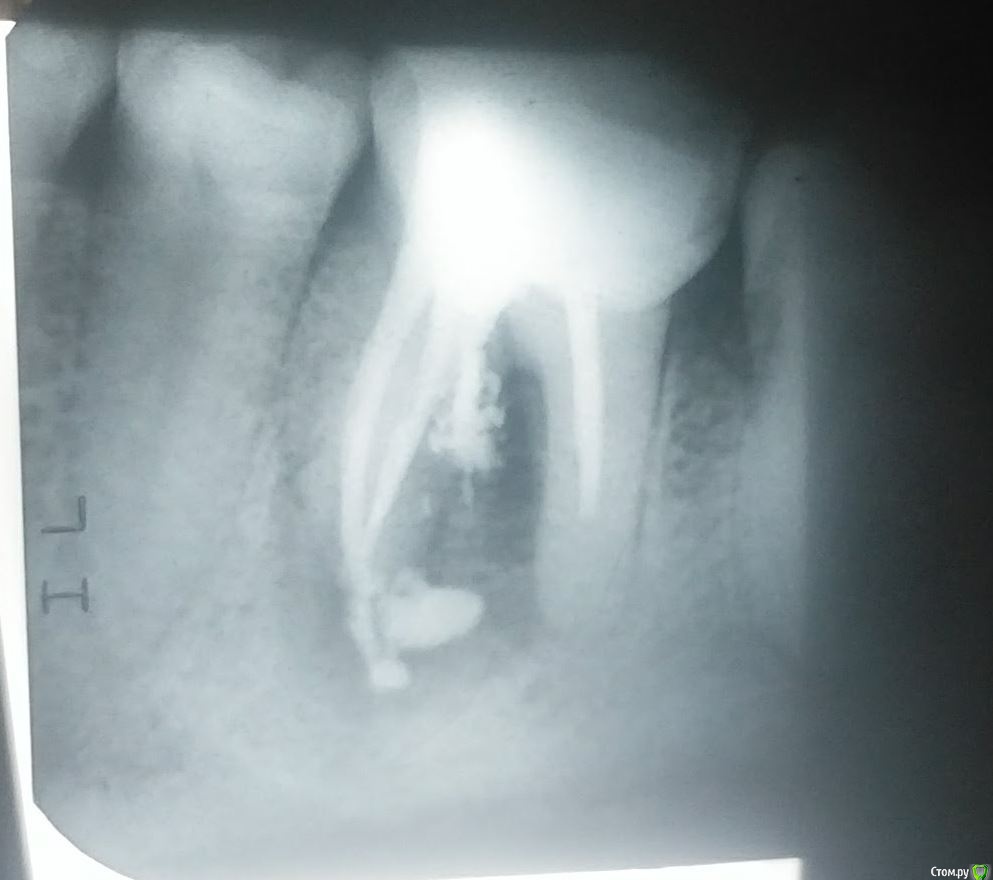

pru2009 Опубликовано 21 февраля, 2018 Поделиться Опубликовано 21 февраля, 2018 Три года тому назад были удалены нервы и установлена пломба на зуб и все было хорошо, но неделю тому назад стало болеть. При обследовании сказали что киста. Стоматолог предложил удаление зуба, но после просьб все-таки заложил лекарство для лечения кисты. Пару дней сильно болело, сейчас боль ушла, опухлость почти прошла, хотя и есть, предлагает на следующей неделе достать лекарство и запломбировать - потом под наблюдение для лечения. Сегодня делал рентген и консультировался с другим стоматологом, он категорически рекомендует удалять зуб и ставить имплант. Посмотрите снимки (это сегодня, лекарство все еще внутри зуба), какое ваше мнение стоит удалять или все-таки можно лечить? Просто жалко зуб удалять если можно вылечить. Ссылка на комментарий

pru2009 Опубликовано 23 февраля, 2018 Автор Поделиться Опубликовано 23 февраля, 2018 если перфорацию надежно закрыть, то еще постоит. Не будьте столь кровожадны )) Меня второй стоматолог напугал тем что на снимке видно что лекарство вытекло в десну, и это якобы ведет к повреждению кости, он меня вообще чуть ли не срочно отправлял на удаление зуба, только стоматолог-хирург к которому направили не взял телефон (видимо готовился к праздникам) поэтому я все еще с зубом.Но сейчас прочитал про перформацию - а получится ли ее закрыть, это ведь получится нужно сейчас убрать лекарство которое вытекло и закрыть канал так чтобы пломбирующий материл тоже не вытек, это без вскрытия десны и операции возможно ли? имею в виду только работая сверху зуба через каналы? или требуется какая-то специфическая операция? Ссылка на комментарий

St. Опубликовано 23 февраля, 2018 Поделиться Опубликовано 23 февраля, 2018 Удалять, закрытие перфорации не решит проблему воспаления между корнями. Если оставить ничего не делая может разболеться в любой неподходящий момент и тогда придется удалять по скорой 1 Ссылка на комментарий

Bier Опубликовано 26 февраля, 2018 Поделиться Опубликовано 26 февраля, 2018 лекарство жить не мешает, оно и рассосаться может постепенно.Если перфорацию надежно закрыть (если это возможно конечно) то и проблема "между корнями" заживет. Ссылка на комментарий